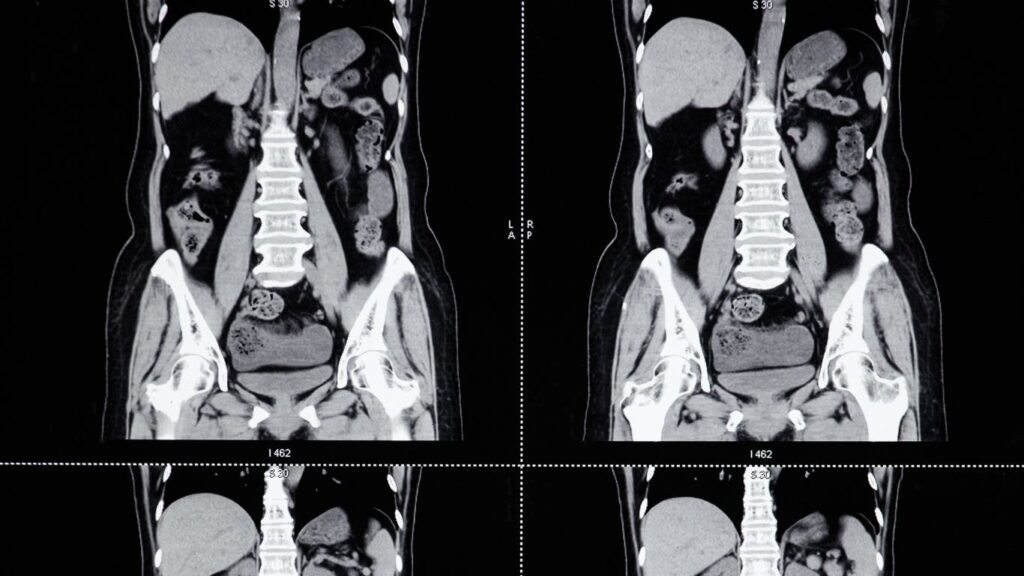

Tomografía Simple de Abdomen en Querétaro

La tomografía simple de abdomen es una herramienta diagnóstica crucial que nos permite visualizar diversas condiciones que afectan los órganos internos del abdomen. En Querétaro, ofrecemos esta prueba en Altaria, garantizando un servicio de alta calidad, que asegura rapidez y precisión en cada diagnóstico abdominal. Nuestra tecnología avanzada y personal capacitado aseguran que cada paciente […]